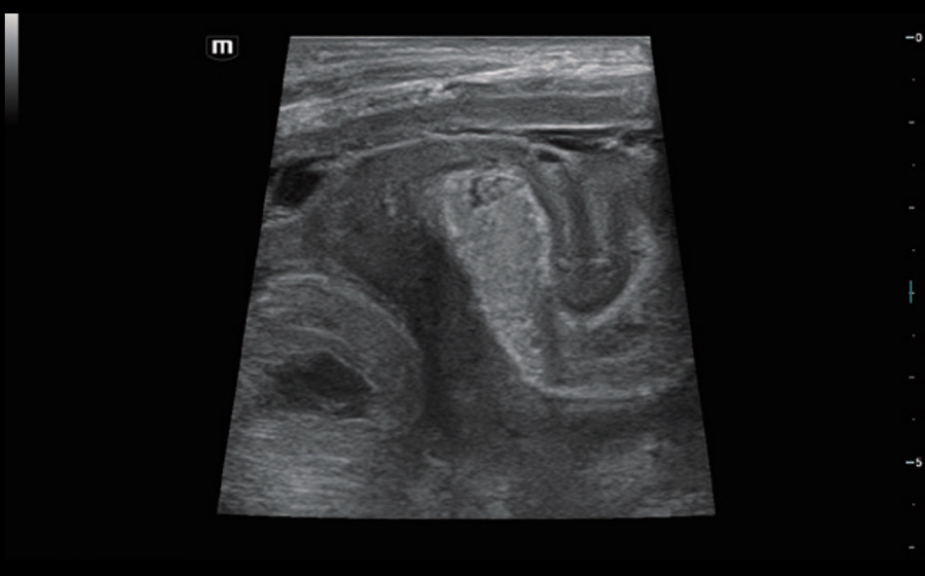

HiFR STE –Ĺ–ĺ–≤–ĺ–ĺ–Ī—Ä–į–∑–ĺ–≤–į–Ĺ–ł—Ź –ľ–ĺ–Ľ–ĺ—á–Ĺ–ĺ–Ļ –∂–Ķ–Ľ–Ķ–∑—č

HiFR STE –Ņ–Ķ—á–Ķ–Ĺ–ł

HiFR STE –Ĺ–ĺ–≤–ĺ–ĺ–Ī—Ä–į–∑–ĺ–≤–į–Ĺ–ł—Ź –ľ–ĺ–Ľ–ĺ—á–Ĺ–ĺ–Ļ –∂–Ķ–Ľ–Ķ–∑—č

HiFR STE –Ņ–Ķ—á–Ķ–Ĺ–ł